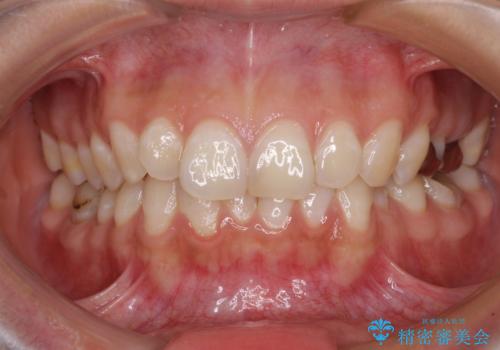

【モニター】隠れている下顎の前歯をインビザラインで改善

- 下顎の前歯が隠れていることと、デコボコを気にして来院された患者様です。

咬み合わせと目立っていた銀歯が改善され、患者様には大変満足していただきました。